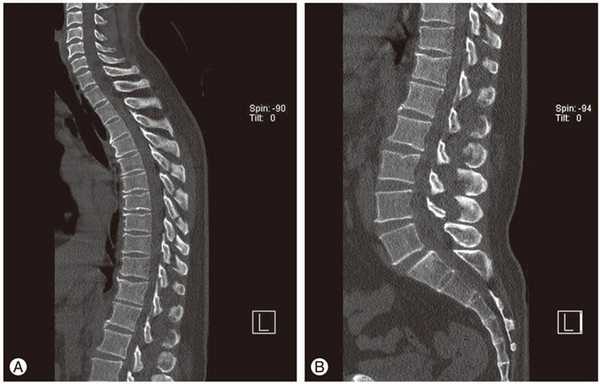

Диагностику остеохондроза позвоночника проводит невролог или вертебролог. На начальном этапе производят рентгенографию позвоночника в 2-х проекциях. При необходимости могут сделать съемку отдельного позвоночного сегмента и съемку в дополнительных проекциях. Для диагностики межпозвонковой грыжи, оценки состояния спинного мозга и выявления осложнений остеохондроза применяют магнитно - резонансную томографию (МРТ позвоночника). Большую роль играет МРТ в дифференциальной диагностике остеохондроза и других заболеваний позвоночника: туберкулезный спондилит, остеомиелит, опухоли, болезнь Бехтерева, ревматизм, инфекционные поражения. Иногда в случаях осложненного остеохондроза шейного отдела позвоночника необходимо исключение сирингомиелии. В некоторых случаях при невозможности проведения МРТ показана миелография.

МРТ поясничного отдела позвоночника. 1- выраженная дегидратация межпозвонковых дисков во всех сегментах. 2- дегидратация в сегментах L3-L4, L4-L5 справа (разные пациенты)

Прицельное исследование пораженного межпозвонкового диска возможно при помощи дискографии. Электрофизиологические исследования (вызванные потенциалы, электронейрография, электромиография) применяют для определения степени и локализации поражения нервных путей, наблюдения за процессом их восстановления в ходе терапии.